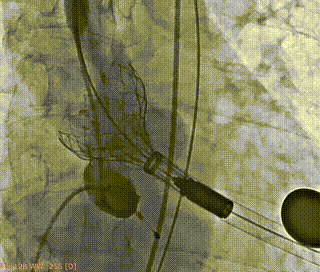

术前造影(左右窦重合体位)

释放支撑臂

支撑臂释放后定位

瓣叶交界贴合释放瓣膜

23mm球囊后扩

最终造影评估